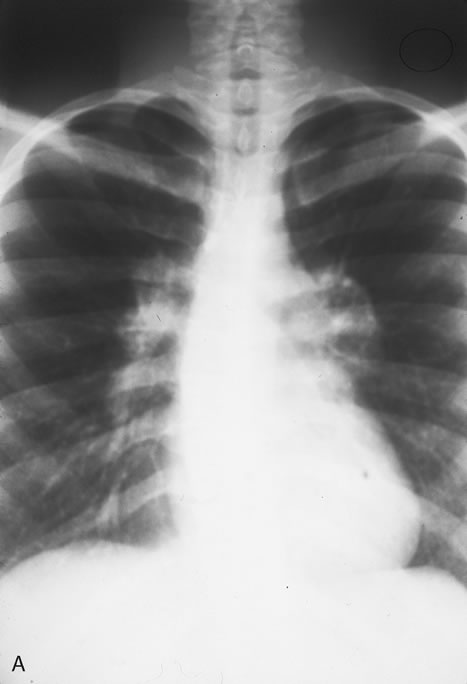

Pneumocystis carinii pneumonia once was the most common presentation of AIDS. It is typically of insidious onset, with features including dry cough, dyspnea, and a diffuse bilateral interstitial infiltrate evident on a chest roentgenogram. Typical multifocal fundus lesions have been described. They are yellow-white and have a characteristic pattern on fluorescein angiography (Fig. 10A, 10B, and 10C). Diagnosis is made by demonstrating the protozoon via sputum induction, bronchioalveolar lavage, and transbronchial or open-lung biopsies. Treatment modalities include trimethoprim-sulfamethoxazole (TMP-SMX).31

Fig. 10. A. The retinal involvement of Pneumocystis carinii is manifested by multifocal, yellow-white lesions. B and C. On fluorescein angiography, the lesions fail to delineate in the early phase (B) but stain in the late phase (C).